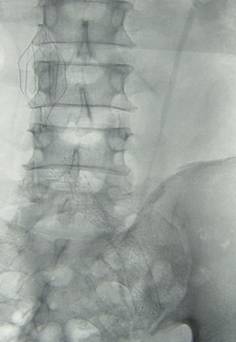

(四)血管疾病介入治疗:一桥飞架南北,天堑变通途

我科已常规开展外周血管介入手术,如对具有高危肺栓塞风险的下肢深静脉血栓形成病人,行下腔静脉滤器置入+置管溶栓术,治疗完成后行下腔静脉滤器取出,对下肢动脉缺血病人行球囊扩张+支架置入术,取得了良好的效果并积累了丰富的临床经验。